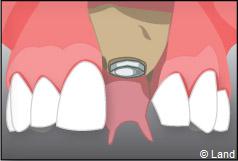

À l’issue de sa mise en place chirurgicale, une bague de cicatrisation en titane peut être directement vissée sur l’implant. Ainsi une seconde chirurgie ne sera pas nécessaire pour découvrir l’implant.

La technique en une seule étape chirurgicale n’est pas toujours possible, c’est à votre chirurgien-dentiste de prendre la décision.